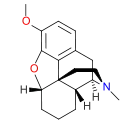

Oripavine derivatives

Thienorphine

- 7-PET

- Acetorphine

- Alletorphine (N-allyl-noretorphine)

- BU-48

- Buprenorphine

- Buprenorphine-3-glucuronide

- Cyprenorphine

- Dihydroetorphine

- Etorphine

- Homprenorphine

- 18,19-Dehydrobuprenorphine (HS-599)

- N-cyclopropylmethylnoretorphine

- Nepenthone

- Norbuprenorphine

- Norbuprenorphine-3-glucuronide

- Thevinone

- Thienorphine

Structures

| Oripavine derivatives | ||||